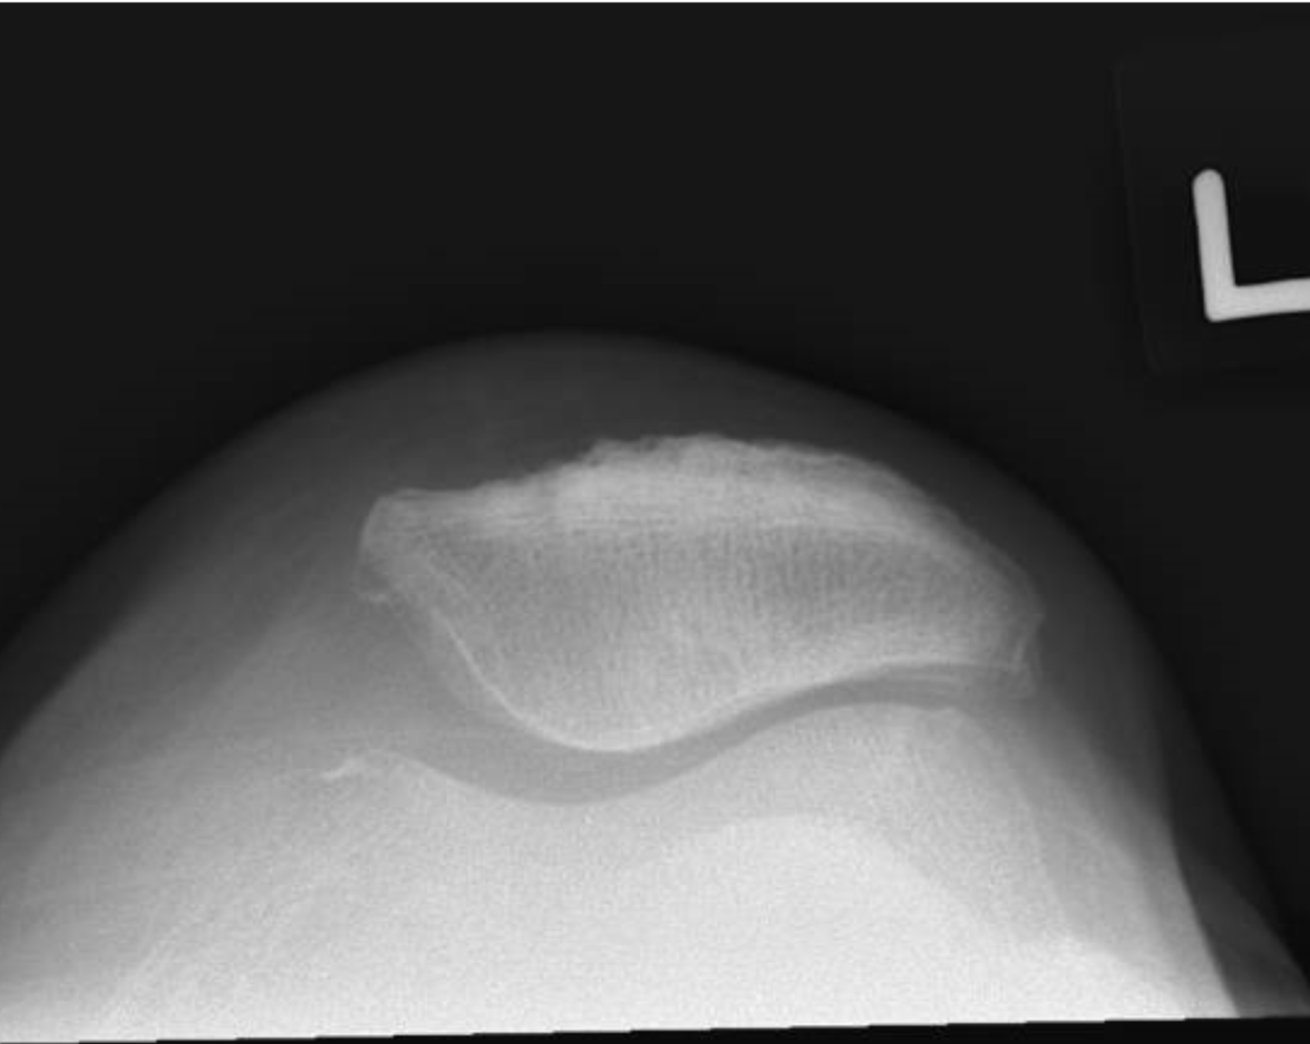

Mako Robot Assisted Knee Replacement Over the years, knee replacement techniques and instrumentation have undergone countless improvements. mako robotic arm assisted surgery system is an example of how technology is transforming the way joint replacement surgeries are being performed. Our mako robotic system delivers enhanced surgical precision through personalized 3d modeling of your knee, created from a preoperative ct scan—this allows your surgeon to plan exact implant placement based on your unique bone anatomy, ligament tension, and joint mechanics. What is mako® robotic arm assisted knee surgery? the mako® surgical system is an innovative robotic tool that allows your consultant to perform knee replacement surgery with greater accuracy and precision than is possible with traditional techniques. Robotic joint replacement improves surgical precision and implant alignment, leading to better long term outcomes. robotic assisted knee joint replacement surgery uses 3d planning and real time guidance for highly personalised treatment. robotic knee replacement surgery reduces tissue damage and supports faster recovery compared to traditional methods. advanced systems, such as the mako robot. Your doctor may recommend robotic knee replacement surgery (also called mako robotic knee replacement surgery). this cutting edge procedure uses advanced technology to assist surgeons to perform more precise and accurate joint replacements. What is mako™ robotic assisted surgery? mako™ robotic assisted surgery is an advanced surgical technique that uses state of the art robotic technology to assist surgeons in performing partial or total knee replacements.